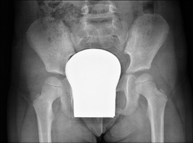

- Pelvis X-ray

This procedure uses X-ray imaging to examine the pelvis, especially the pelvic bones.

- Sacroiliac X-ray

This procedure uses X-rays to examine the sacroiliac joints and rule out inflammatory, traumatic or degenerative diseases.